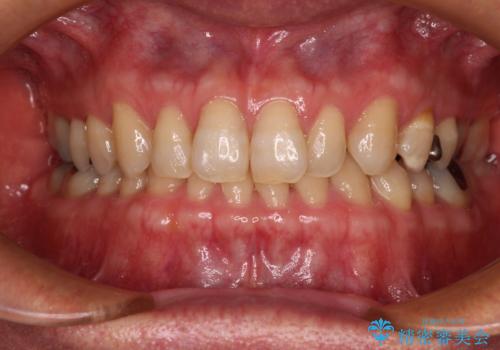

捻れて前に出ている前歯 ワイヤー装置での非抜歯矯正